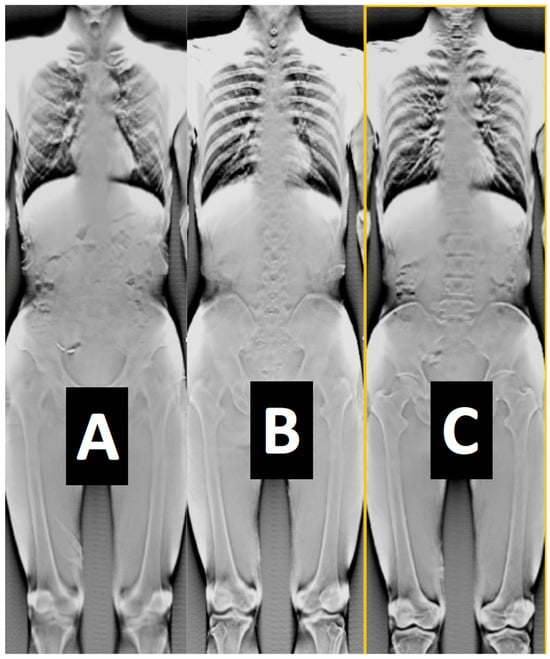

| 2D radiography (see Figure 5, Figure 6, Figure 11 and Figure 16) | See detector a, b, c resolution | 1 s to 2 min/1–360 | ~50/50/50 | SID 50–1100/ everything else is variable |

| 3D CT (Figure 2 and Figure 12) | 80–200 μm full CT, 3x mode CT, half-beam mode, stacked-volume mode | 6 s to 4 min/40–5000 | ~50–500/16.4–200/62–120 Total dose in full in vivo high-res. CT: 6.2 mSv | 700/480/240/0.06 |

| 3D tomosynthesis (see Figure 2 and Figure 11). Optical mag., x4 | 10–40 μm fixed detector, moving emitter | 6 s to 2 min/5–5000 | ~30/16.4/34 | 50–1100/variable SOD/variable VD and VH/0.02–0.2 |

| 3D dynamic imaging stereovideography (Figure 5, Figure 6 and Figure 9) | 20–200 μm Static or moving image intensifiers with high-speed cameras | 1 s, as required by IR/10–10000 | 0.02–1.1 mSv min−1/0.08–0.9 mSv min−1/0.02–0.08 mSv min−1 | 50–1100 /10–500/variable VD and VH/0.02–0.2 |

| 3D “microCT” optical and geometrical magnification x4 (Figure 2 and Figure 13) | 0.02 mm Emitter/detector rotation only | 1 min to 5 min or as required/100–5000 | 0.2–5 mSv min−1/not available/0.2–5 mSv min−1 | 50–100 /10–50/variable VD and VH/0.02 |